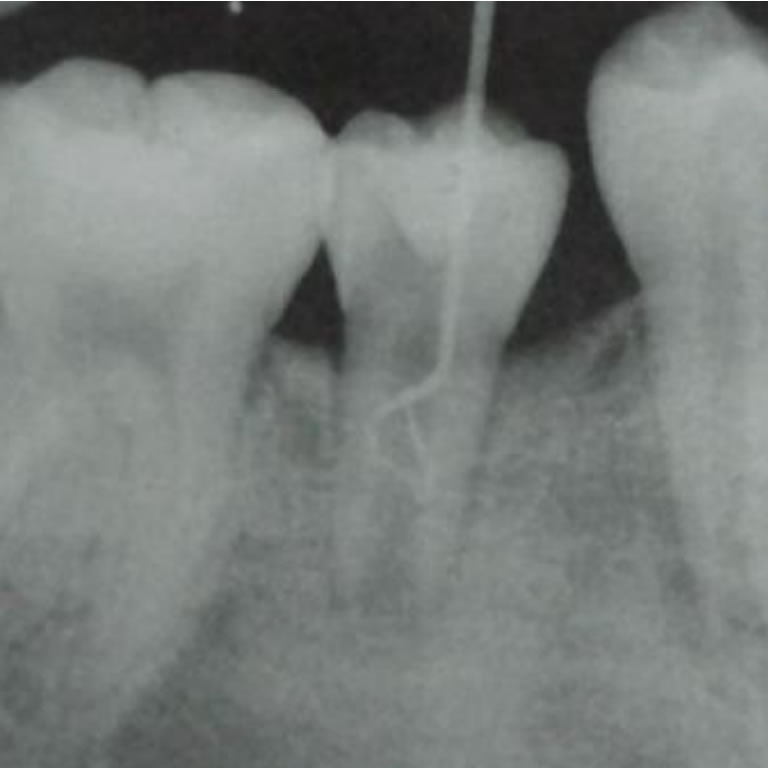

Biofilms en Endodoncia

Dr. Gustavo H. Lopreite

El artículo describe los biofilms como comunidades microbianas complejas adheridas a los conductos radiculares, con matriz protectora que les confiere alta resistencia a desinfectantes. Su persistencia dificulta el éxito de la endodoncia, por lo que eliminarlos es clave para el tratamiento eficaz.